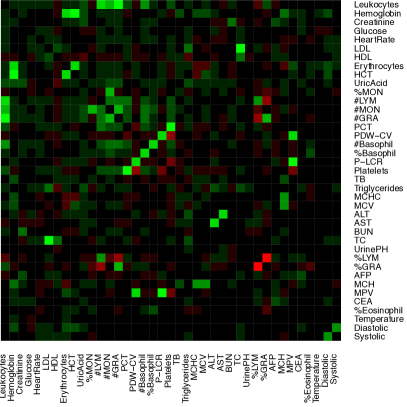

The data contain blood test results measured on 39 testing items which are listed in Table 1. Figure 1(a) shows the empirical correlation structure of the testing items as a heatmap with green, black, and red colors indicating positive, negligible and negative correlations. With appropriate ordering of the test items, one can see some patterns on the upper-left corner of the heatmap. However, the patterns seem vague and have no clear interpretation. The heatmap of the standardized data is shown in Figure 1 with green, black and red colors indicating values above, near and below the average. Next we cluster the data using a K-means algorithm with (the number of latent diseases identified in later model-based inference), applied to both, rows and columns of the data matrix. The clusters find some interesting structures. For example, indexing the submatrices in the heatmap by row and column blocks, the values in block (9,9) tend to be above the average, whereas the values in the block (1,4) tend to be below the average. However, there are at least two difficulties in interpreting the clusters as latent diseases. Firstly, there is no absolute relationship between the normal range of a testing item and its population average. A deviation from the average does not necessarily indicate an abnormality. Likewise, average values of testing items, especially those related to common diseases such as hypertension, are not necessarily within the normal range. For instance, the mean and the median of systolic blood pressure in our dataset are 147 mm Hg and 145 mm Hg, both of which are beyond the threshold 140 mm Hg for hypertension (the high blood pressure values might be related to the elderly patient population). Secondly, the exploratory analysis with K-means does not explicitly model patient-disease relationships and symptom-disease relationships. For example, one may be tempted to interpret each column block as a latent disease. As a consequence, each testing item has to be associated with exactly one disease and the patient-disease relationship is unclear. If instead, we define a latent disease by the row blocks, then each patient has to have exactly one disease and the symptom-disease relationship is ambiguous.

We can slightly improve interpretability by incorporating prior information. Specifically, each testing item comes with a reference range which we use to define symptoms: a symptom is an item beyond the reference range. In essence, we convert the original data matrix into a ternary matrix which is shown in Figure 1. The first difficulty is resolved but the second difficulty remains. For instance, the 6th column seems to suggest a disease with elevated total cholesterol and low density lipoproteins, which is also found in our later analysis with the proposed DFA. However, just as in Figure 1, it is hard to judge which blocks meaningfully represent latent disease since patient-disease relationships and symptom-disease relationships are not explicitly modeled. Besides the requirement of specifying the number of clusters, K-means is unsuitable for the task that we are pursuing in this paper.

Alternatively, instead of discretization, we can scale and center test items at the midpoint of each reference range. We show the heatmap in Figure 1 where the rows and the columns are arranged in the same way as in Figure 1. However, just as previous cases, the same limitation of interpretability still applies.